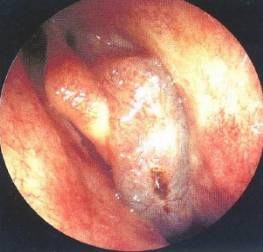

1、内镜检查:来源于中鼻道、嗅裂的黏脓性分泌物,中鼻道粘膜充血、水肿或有鼻息肉。

- 鼻腔检查:前鼻镜、鼻内窥镜。